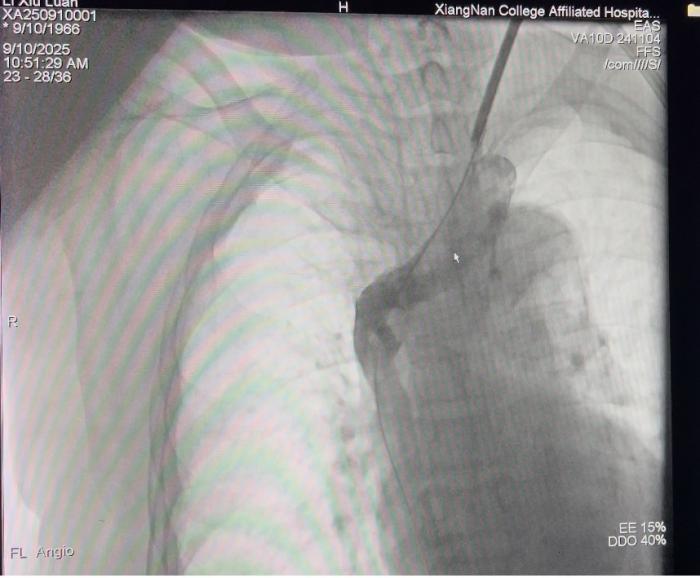

闭塞开通前的影像

上腔静脉闭塞开通后的影像